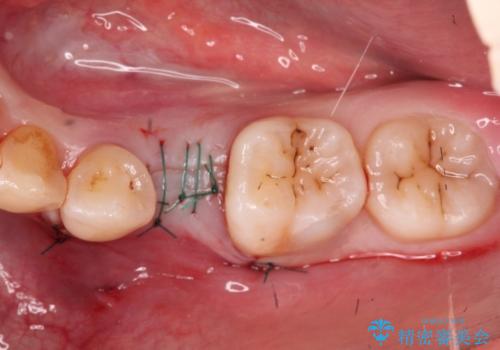

小臼歯のインプラント

- 20代女性

- 6ヶ月

- 小臼歯が先天性欠損していたため、インプラントにて補綴しています。

当院ではストローマンインプラントを導入しています。